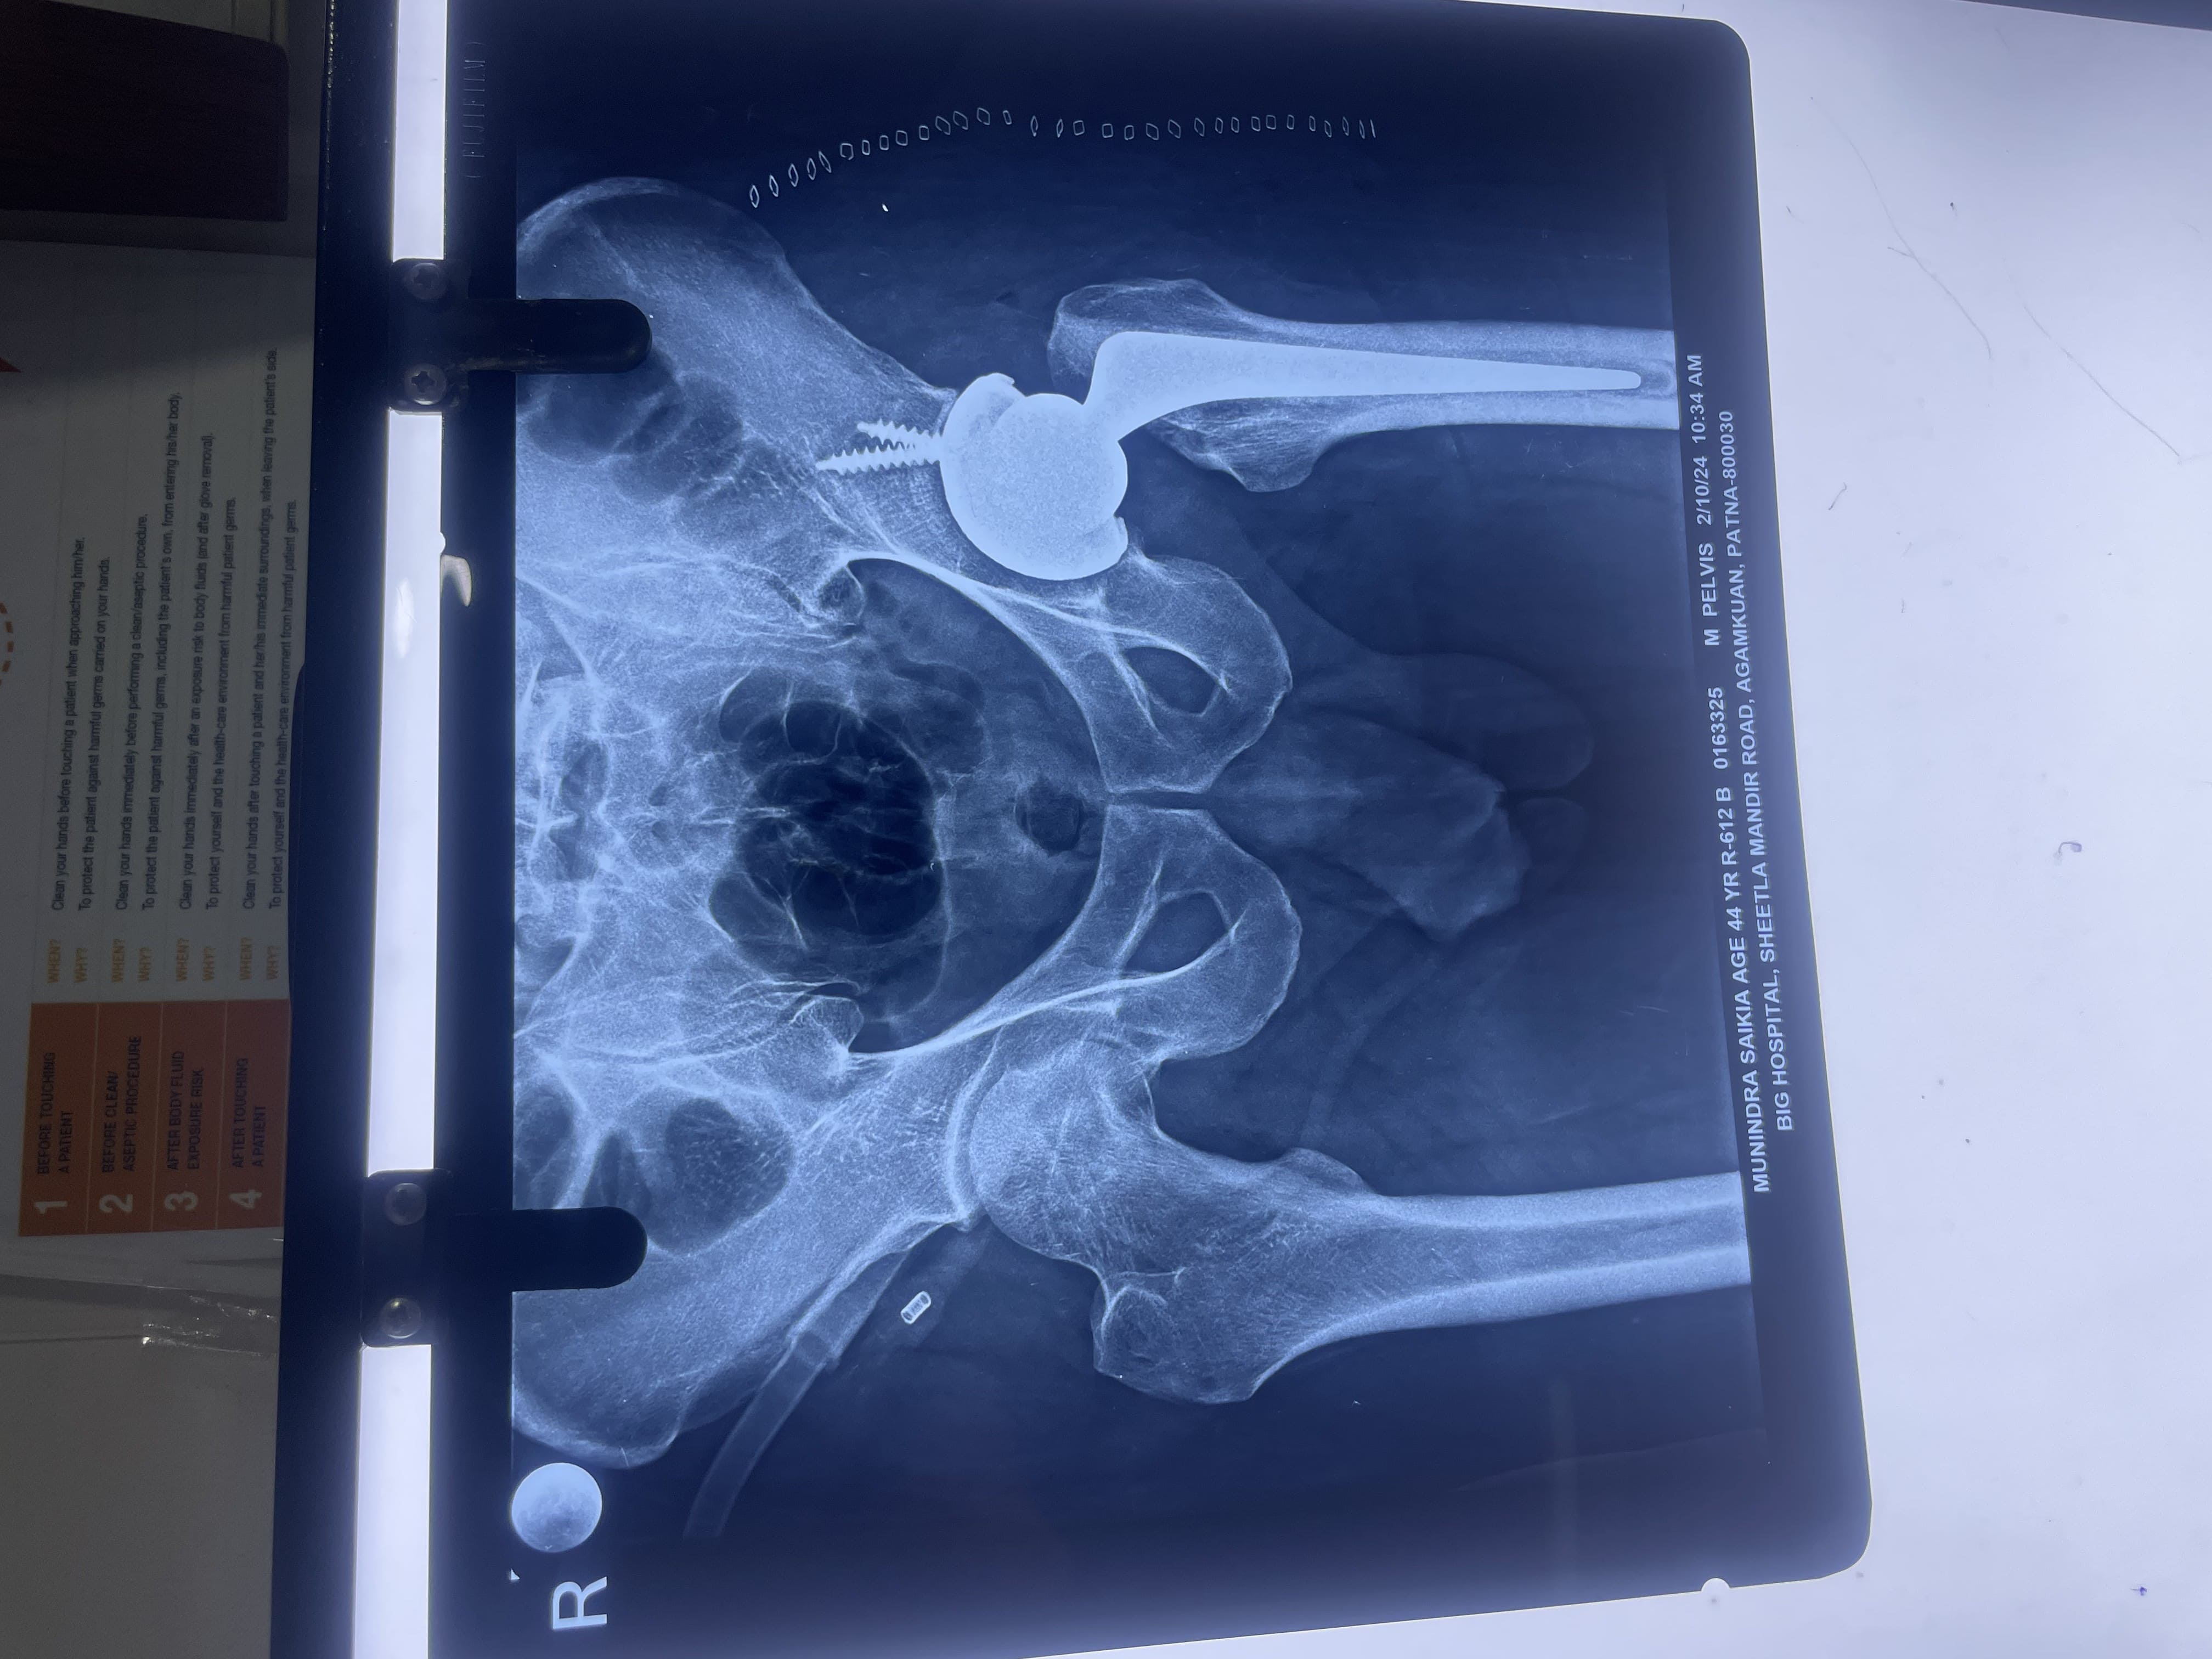

Periprosthetic Joint Fracture Management, Complex and Periarticular Fracture Management